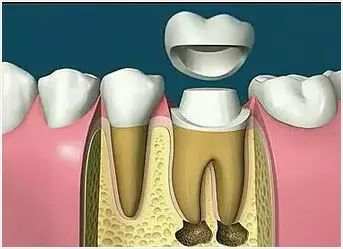

7、根管打桩 因牙体缺损过多,导致牙的强度(承受力量的性能)大幅度下降,不能很好地承受咀嚼力量。打桩的目的是增加牙根及牙冠的强度,增加患牙的稳固。 8、完成牙体修复 X线片显示根管充填完好,行暂时或永久牙体修复,带上牙冠,保护患牙。至此根管治疗才可算完成,同时根管治疗后还需复诊,一般周期可为3个月、半年、1年、2年或更长。